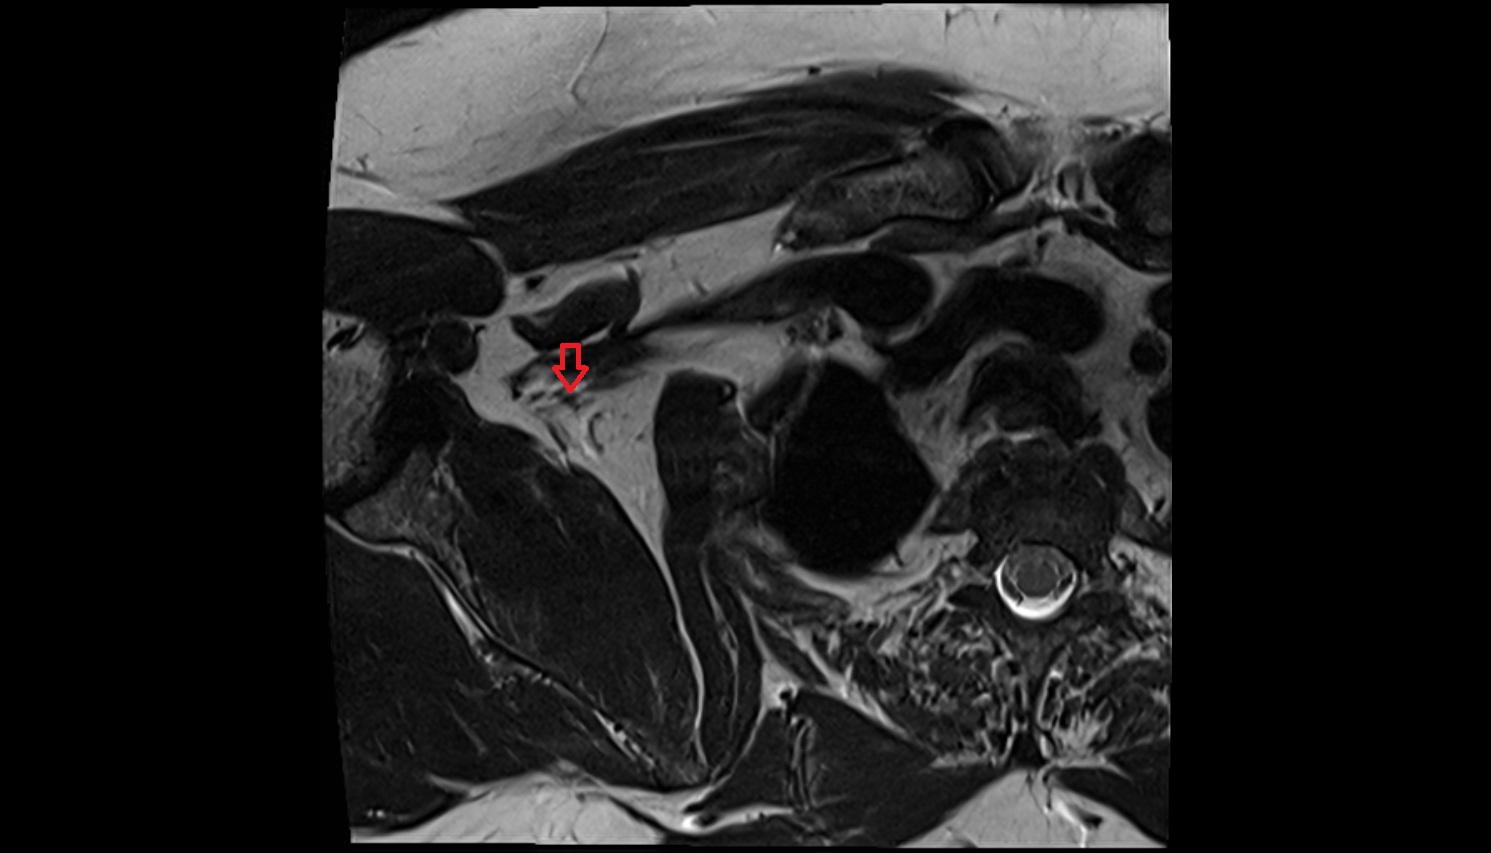

- Hip joint